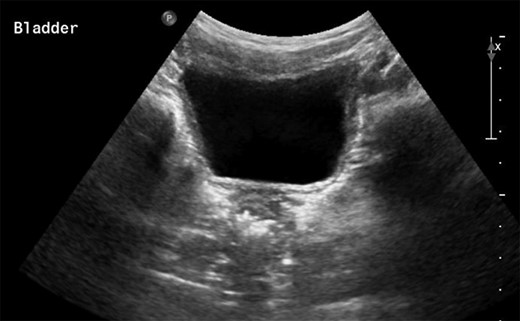

The patient presented 2 weeks post-operatively with enlargement of the scrotal hydrocele. A non-communicating encysted component was suspected. A watchful waiting approach was planned but the swelling grew further so a Jaboulay procedure was performed. After postoperative swelling had resolved it was clear that the scrotal hydrocele persisted. After 2 months an ultrasound scan (USS) was performed and was largely insignificant other than the identification of the scrotal hydrocele itself (Fig. 1).